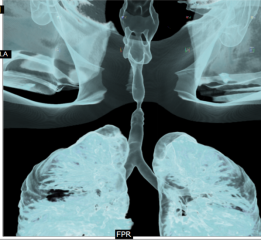

A 6-year-old female child presented to our clinic with progressive breathlessness and stridor for a duration of 5 days. She had a recent history of road traffic accident and sustained head injury and underwent craniotomy for extradural hemorrhage. Post-surgery she was on mechanical ventilator support for 10 days after which she was extubated. She developed stridor after 7 days of extubation. CT Neck revealed focal hour-glass configuration, concentric asymmetrical subglottic narrowing with associated soft tissue thickening 2-3cm below the level of vocal cords, with a diameter of 4.5 x 5.0 mm (AP X TR) at the point of maximal narrowing. Diagnostic flexible bronchoscopy showed circumferential stenosis (Grade III Myers-Cotton) of subglottic area about 2.5 cms below the glottis and we could not negotiate beyond the level of stenosis.

Rigid bronchoscopic repair of the stenosis was performed combining serial rigid bronchoscopic dilatations and balloon bronchoplasty using CRE dilatation balloons of varying sizes. Post dilatation, we were able to negotiate the rigid bronchoscope beyond the level of stenosis and were able to achieve a lumen of 100% with no residual stenosis. Follow-up CT Neck showed normal caliber of tracheal lumen with a luminal diameter of 8.6 x 8.3 mm at the level of previous narrowing. Total reduction of the clinical stridor was observed post procedure. Surveillance bronchoscopy after 4 weeks showed no further narrowing and good patency of tracheal lumen. Patient remained asymptomatic in subsequent follow up visits with improved pulmonary function tests

Radiology Images: